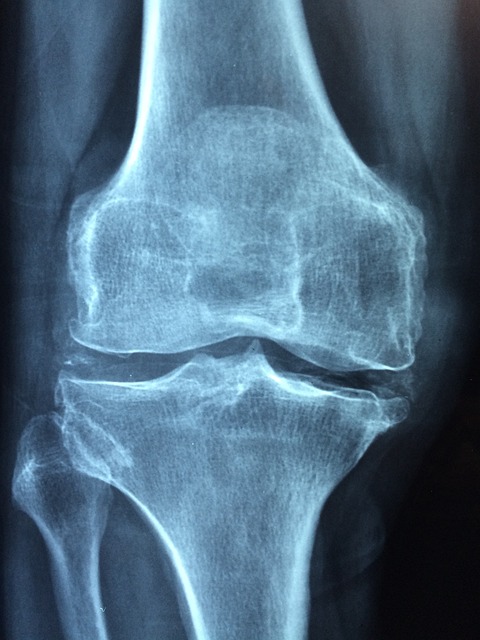

골다공증은 어떻게 진단하나요?

골다공증은 주로 '골밀도 검사(DXA)'를 통해 진단합니다. 이 검사는 뼈의 밀도를 측정하여 골다공증 여부와 그 정도를 파악합니다. 50세 이상의 여성과 고위험군에 속하는 사람들은 정기적인 검진을 받는 것이 좋습니다.